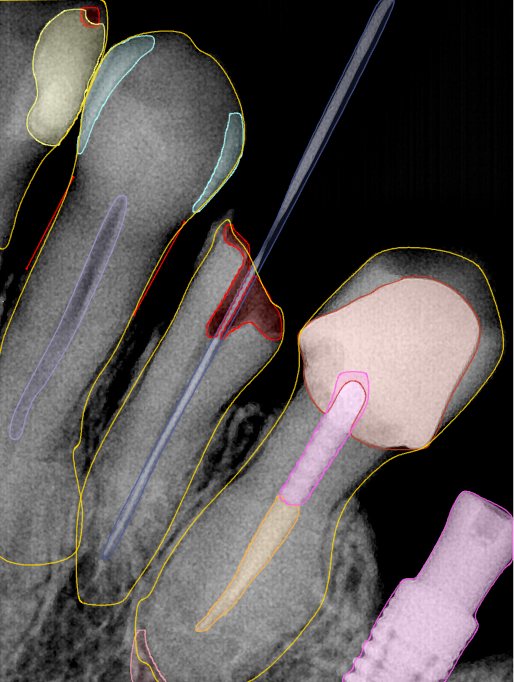

CR/DR 牙齿分割阶段记录

当前进展

- 完成了 CR/DR 牙齿相关分割训练

- 当前结果已经达到阶段预期,但仍有细节问题需要继续处理

相关测试

遇到的问题

- 训练过程中出现过 mask 下移问题

- 部分结果会出现 box 填充异常

- mask 边缘仍然有比较明显的锯齿感

参考

第二版算法问题测试